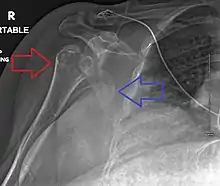

Lightbulb sign indicative of posterior shoulder dislocation shown on the left. On the right, the same shoulder after reduction.

Posterior dislocations are uncommon, and are typically due to the muscle contraction from electric shock or seizure.[5] They may be caused by strength imbalance of the rotator cuff muscles. People with dislocated shoulders typically present holding their arm internally rotated and adducted, and exhibiting flattening of the anterior shoulder with a prominent coracoid process.

Posterior dislocations may go unrecognized, especially in an elderly person[11] and in people who are in the state of unconscious trauma.[12] An average interval of 1 year was noted between injury and diagnosis in a series of 40 people.[13]